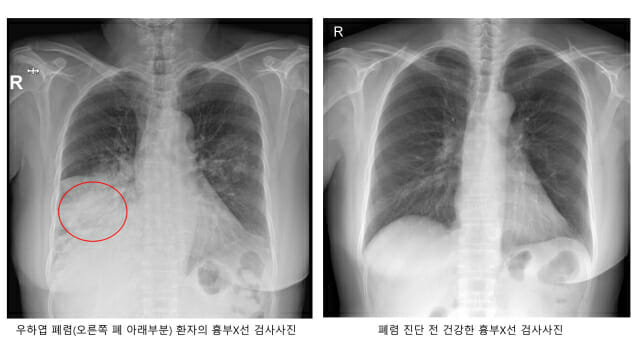

폐렴은 세균이나 바이러스가 폐로 침투해 염증이 생긴 질환을 말한다. 폐렴구균에 의한 세균성 폐렴이 흔한데, 폐렴구균은 평소에도 코와 목의 점막에 상주하기 때문이다. 몸의 면역력이 약해지면 폐·뇌·혈관·귀 등에 침투해 폐렴과 수막염 등을 일으킨다.

폐렴 초기 증상은 발열·기침·가래 등 일반 감기와 비슷하다. 그렇지만 폐렴구균이 본격적인 활동을 시작하면 고열·기침·가슴 통증·호흡곤란을 유발한다. 숨이 가빠지면 호흡수도 많아져 분당 20회를 넘게 된다.

폐렴구균에 의한 폐렴일 경우, 가래 색깔이 적갈색으로 진하게 바뀌기도 한다. 뿐만 아니다. 폐렴에 의해 폐가 손상되게 되면 산소교환 기능이 저하되게 되고, 그로 인해 혈액 속에 산소 농도가 떨어진다. 이에 따라 입술이 푸른빛으로 변하는 ‘청색증’은 폐렴 합병증의 증상이다. 이 상황에 이르면 생명이 위험할 수 있어서 반드시 병원에서 전문적인 치료를 받아야 한다.

건강한 성인은 항생제 치료와 적당한 휴식만 취하면 쉽게 나을 수 있다. 그렇지만 고령층은 폐 기능과 면역력이 떨어져 있으므로 한번 폐렴에 걸리면 중증으로 이어지는 경우가 많다. 폐렴이 악화해 호흡부전으로 이어져 인공호흡기 치료를 받거나 패혈증으로 혈압이 떨어져 치명적인 쇼크에 이르기도 한다. 다발성 장기부전은 더 위험하다.